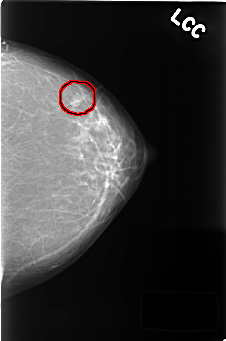

C_0382_1.LEFT_CC

LEFT_CC LINES 4424 PIXELS_PER_LINE 2928 BITS_PER_PIXEL 12 RESOLUTION 50 OVERLAY

FILE: C_0382_1.LEFT_CC.OVERLAY

TOTAL_ABNORMALITIES 1

ABNORMALITY 1

LESION_TYPE MASS SHAPE OVAL MARGINS CIRCUMSCRIBED

ASSESSMENT 3

SUBTLETY 5

PATHOLOGY BENIGN

TOTAL_OUTLINES 1

BOUNDARY